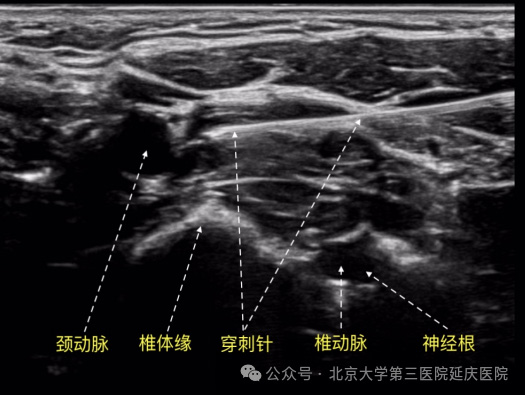

老百姓口中的“鼻炎针”是一种微创的神经调节疗法,指的是在颈部的星状神经节进行精准阻滞。

这是一种微创介入治疗,通常在门诊治疗室内进行,一个常见的治疗周期通常需要4-6次为一个疗程,具体次数需根据患者的反应由医生评估。